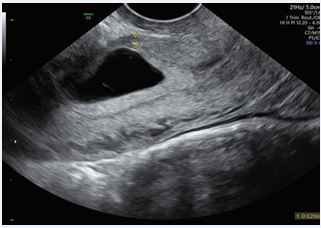

A 29-year-old female presented to our Obstetric Emergency Unit with the main complaint of irregular spotting and vaginal bleeding lasting 7 days. Her medical and surgical history was unremarkable. In her obstetric history, she had undergone a cesarean section at 37 weeks due to fetal distress during induction for an IUGR fetus with trisomy 21. Upon examination, there were no general concerns. At speculum assessment, the cervix appeared normal, with no discharge, and minimal residual uterine bleeding was noted in the vagina. On bimanual examination, the cervix was upward-pointing, the uterus was bulky and anteverted, and the bilateral fornixes were free and non tender. Laboratory tests revealed normal results, with hemoglobin levels within the reference range. A positive β-hCG test indicated a level of 7118 IU/L, which rose to 14,452 IU/L after 48 hours, showing less than a doubling effect. Transvaginal ultrasound performed in the emergency unit showed an empty uterine cavity with clearly defined endometrium. A small, irregular gestational sac-like structure corresponding to five weeks was identified in the lower uterine segment anteriorly, with a vitelline sac and a small embryo without cardiac activity. Both adnexa were normal, and no free fluid was observed in the Douglas pouch. Doppler imaging confirmed the diagnosis of a cesarean scar ectopic pregnancy, revealing excessive vascularity in the hyperechoic rim of the choriodecidual reaction. Ultrasound findings were later corroborated by expert sonographers, with no signs of uterine dehiscence or rupture. Initial management involved monitoring clinical signs and serial β-hCG levels. The patient was asymptomatic, and after thorough counseling regarding pregnancy outcomes (expectant management versus pregnancy interruption), she decided for interruption. Intramuscular Methotrexate was then administered (50 mg/ im). By Day 3, a significant increase in β-hCG levels (22,797 IU/L) and enlargement of the gestational sac (19x17 mm) prompted the decision to administer a single oral dose of 600 mg Mifepristone. Unfortunately, this approach failed to terminate the pregnancy (Figures 1-3). By Day 5, ultrasound imaging confirmed the presence of an embryo with cardiac activity. After additional counseling, the patient consented to a further intervention.

Figure 2: Transvaginal ultrasound- Color Doppler imaging shows vascularization surrounding the gestational sac.